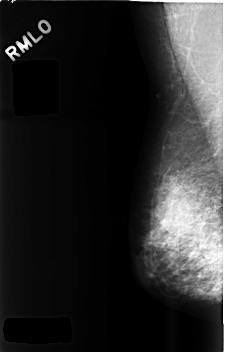

C_0481_1.RIGHT_MLO

RIGHT_CC LINES 4488 PIXELS_PER_LINE 2920 BITS_PER_PIXEL 12 RESOLUTION 50 NON_OVERLAY

RIGHT_MLO LINES 4576 PIXELS_PER_LINE 2920 BITS_PER_PIXEL 12 RESOLUTION 50 NON_OVERLAY